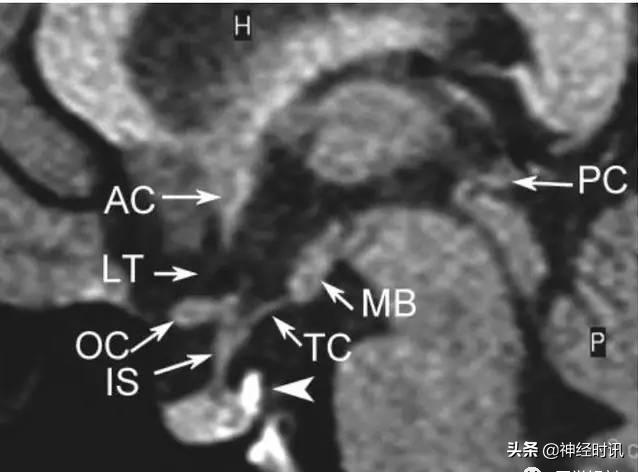

颅脑正中矢状面

AC:前联合;LT:终板 OC:视交叉;IS:漏斗柄;TC:灰结节;MB:乳头体;PC:后联合